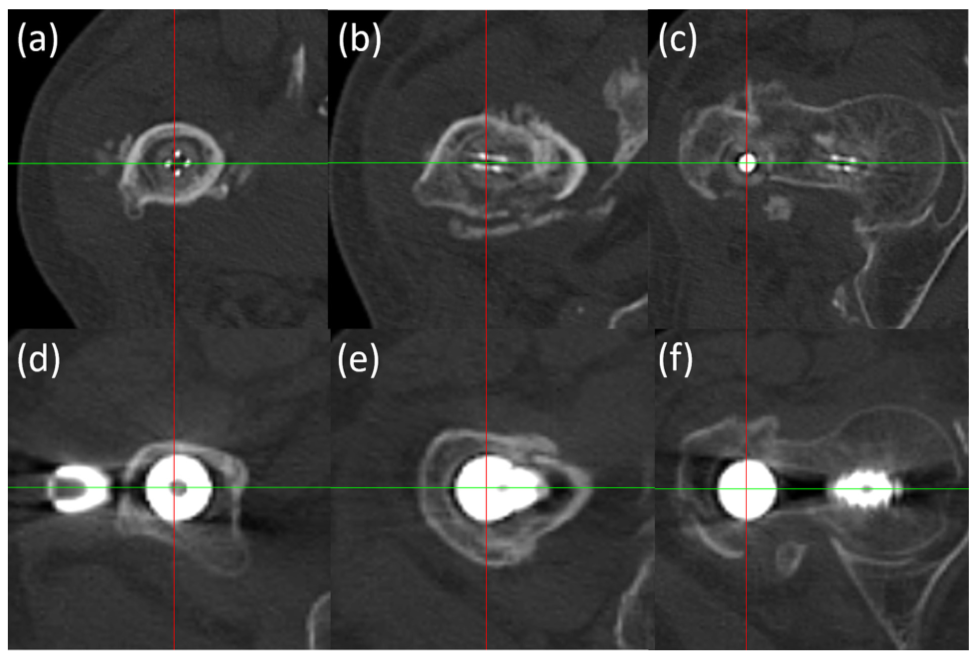

图5 在CT上,金属内植物由于金属散射,导致对骨折线观察存在干扰。